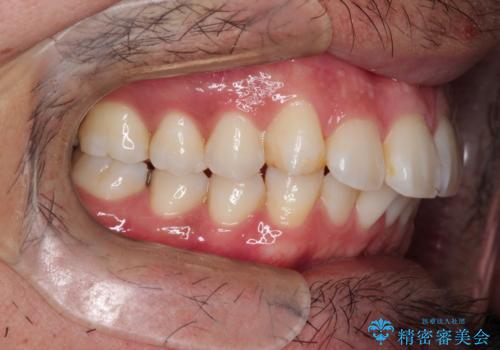

【インビザライン】前歯の凸凹を解消。

- 前歯の凸凹を主訴に来院されました。

もともと、顎が左にシフトしていたので正中が合わないことを説明した後、矯正を開始しています。

短期間で前歯のがたがたがきれいになり、満足していただけました。